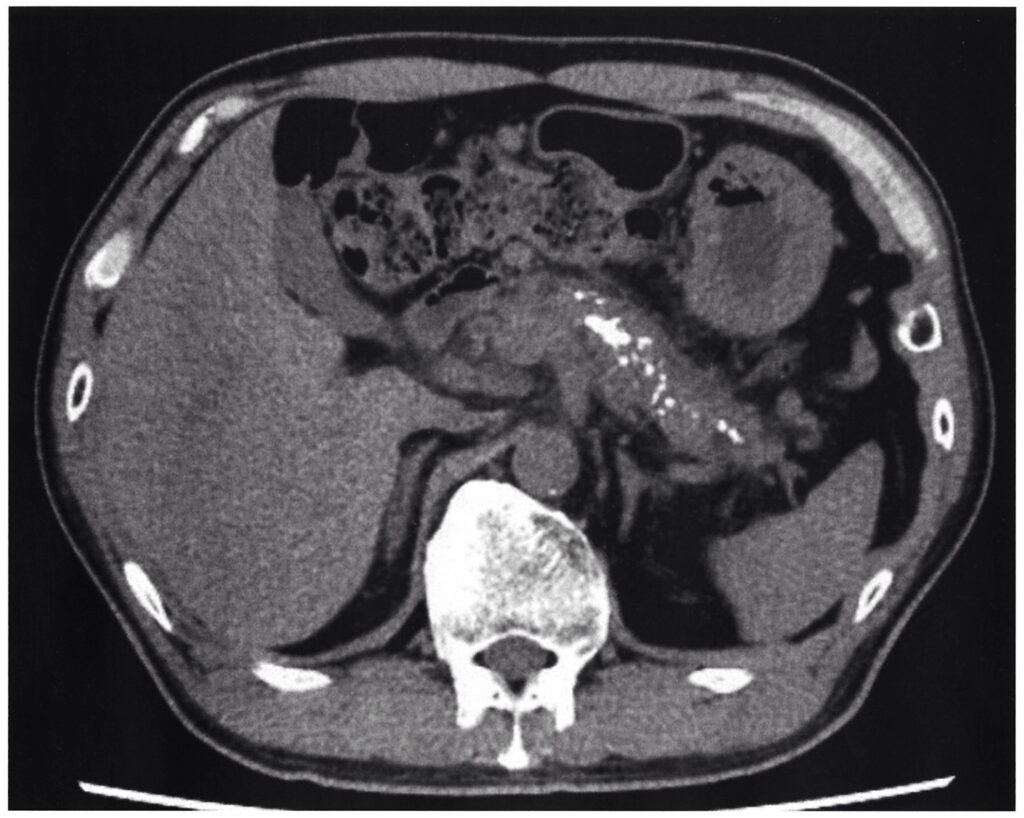

54歳の男性。下痢を主訴に来院した。2ヵ月前から下痢が出現し軽快しないため受診した。便回数は1日に6〜7回、便性状は泥状から水様であり、揚げ物を食べると脂肪便を認める。便に血液の付着はない。飲酒は日本酒 6合/日を34年間。身長174cm、体重58kg。血圧132/70mmHg。腹部は平坦、軟で圧痛を認めない。腸雑音はやや亢進している。血液生化学所見:アミラーゼ 28U/L(基準44〜132)、空腹時血糖140mg/dL、CEA 3.0ng/mL(基準5以下)、CA19-9 37U/mL(基準37以下)。腹部単純CTを次に示す。

問題の概要は、『水様性下痢、脂肪便、アミラーゼ低値、長年の多量飲酒歴、やせ型、CTでの膵石灰化所見から慢性膵炎を疑います。病期によって治療が異なるが対応はどれか?』ということになります。

①長期の飲酒歴、②脂肪便・体重減少などの消化吸収障害、③画像での石灰化や萎縮 が重要です。